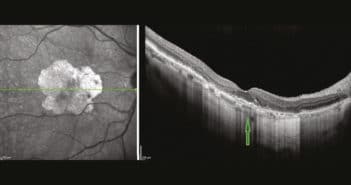

La DMLA atrophique touche en Europe près de 3 % de la population de plus de 60 ans avec des prévisions d’augmentation forte d’ici 2050. L’étiologie est multifactorielle, mélangeant environnement, prédisposition génétique et inflammation. La cible d’un traitement préventif ou ralentissant l’évolution inexorable est donc difficile à trouver, les études cliniques médicamenteuses se focalisant sur des anomalies de la cascade du complément, pour l’instant décevantes.

Quand les cellules visuelles ont disparu, on pourra imaginer l’utilisation de cellules souches rétiniennes en cours de développement mais, pour l’instant, la seule alternative aux stades terminaux est l’utilisation de photorécepteurs artificiels quand il n’y a plus aucune vision centrale. Tous les patients devraient bénéficier d’une rééducation basse vision dès qu’une gêne est notée, améliorant souvent la qualité de vie.